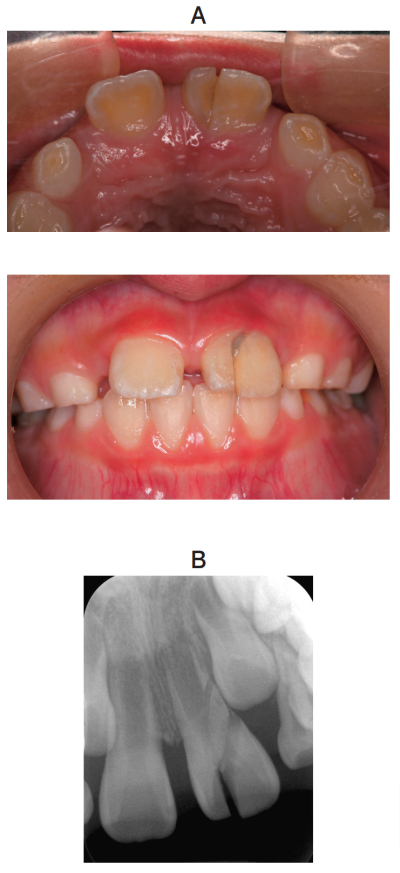

8歳の男児。上顎左側中切歯の外傷を主訴として来院した。昨夕、自転車で転倒し、自発痛が軽度であったため、そのままにしていたという。検査と診断の結果、抜歯を行うこととした。初診時の口腔内写真とエックス線写真を別に示す。

治療方針の根拠はどれか。1つ選べ。

a. 歯根が未完成である。

b. 固定源が確保できない。

c. 歯根膜腔が拡大している。

d. 破折線が歯槽骨縁下である。

e. 受傷から長時間経過している。